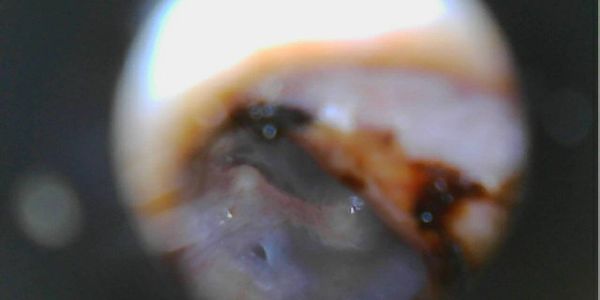

Hannah uses otoscope examination throughout the procedure to ensure safe, complete wax removal.